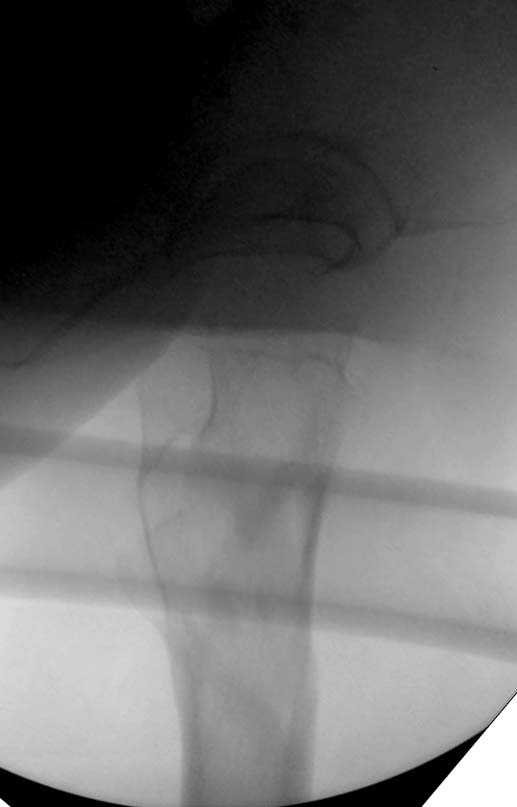

Здесь представлен случай, где в послеоперационном периоде обнаружена техническая ошибка, Gamma 3 установлен с нарушением методики. Больная в 91 лет, прооперирована через день после поступления и выписана через 48 часов.<br>

При первом послеоперационном поликлиническом осмотре больная предъявила жалобы на боли в бедре. В серийных снимках обнаружен продольный перелом верхнего отдела бедра.<br>

Считаем, что техническая ошибка произошла во время установки гвоздя, когда рассверливанию канала не уделили должного внимания. Канал остался узковат, и гвоздь был забит с силой.

Имя     : Gamma 3. 3.jpg